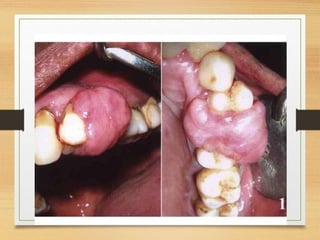

Congenital epulis of new born

• Congenital granular cell lesion.

• Hamartoma

• Rare lesion

• Neuman’s tumor.

• At birth, common in females

• Occurs as a single tumor.

• Alveolar ridges of new born.

• Protuberant mass on the maxilla.

• Malformations of dental blastema(undifferentiated

embryonic tissue) - type of embryonal hamartoma.

• Presence of numerous epithelial rests.

Clinical features

• At birth.

• Maxillary(common) or mandibular gingiva.

• Pedunculated lesion found in the lateral incisor

canine region-crest of the alveolar ridge.

• Pink to red smooth surfaced polypoid mass.

• 2cm or less in size.

• Rarely on tongue